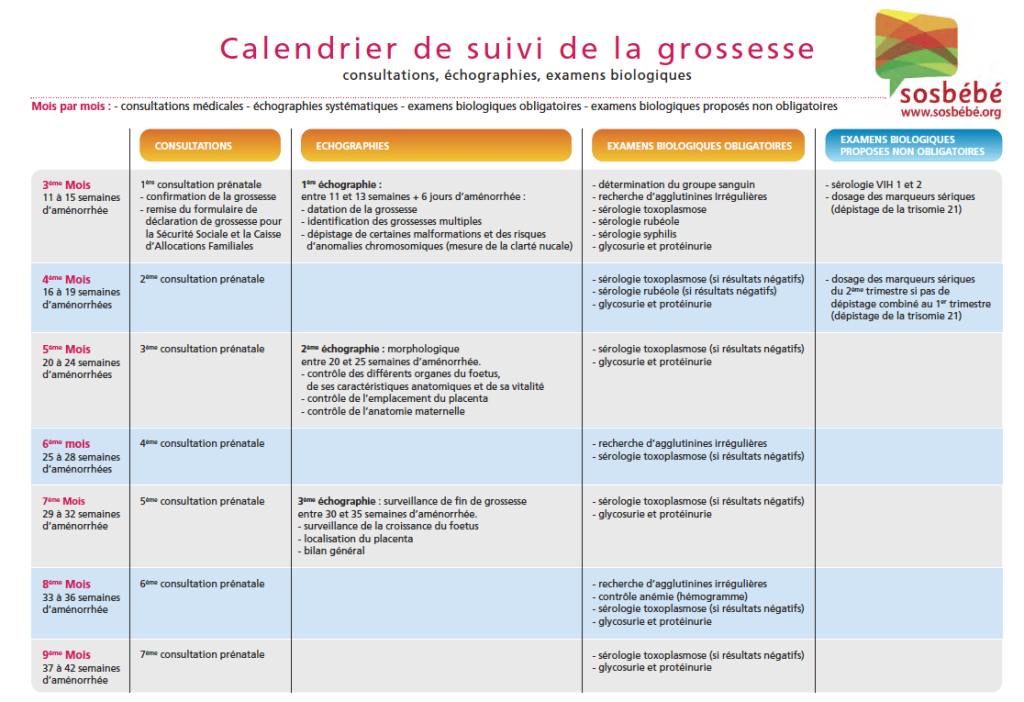

Le calendrier de suivi de la grossesse

Le calendrier de suivi de la grossesse est résumé comme suit :